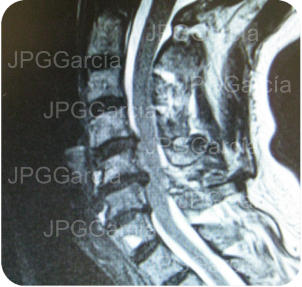

Tratamiento de hernia de disco cervical alta con compromiso medular

Tratamiento microquirúrgico de hernia extruida cervical con mielopatía